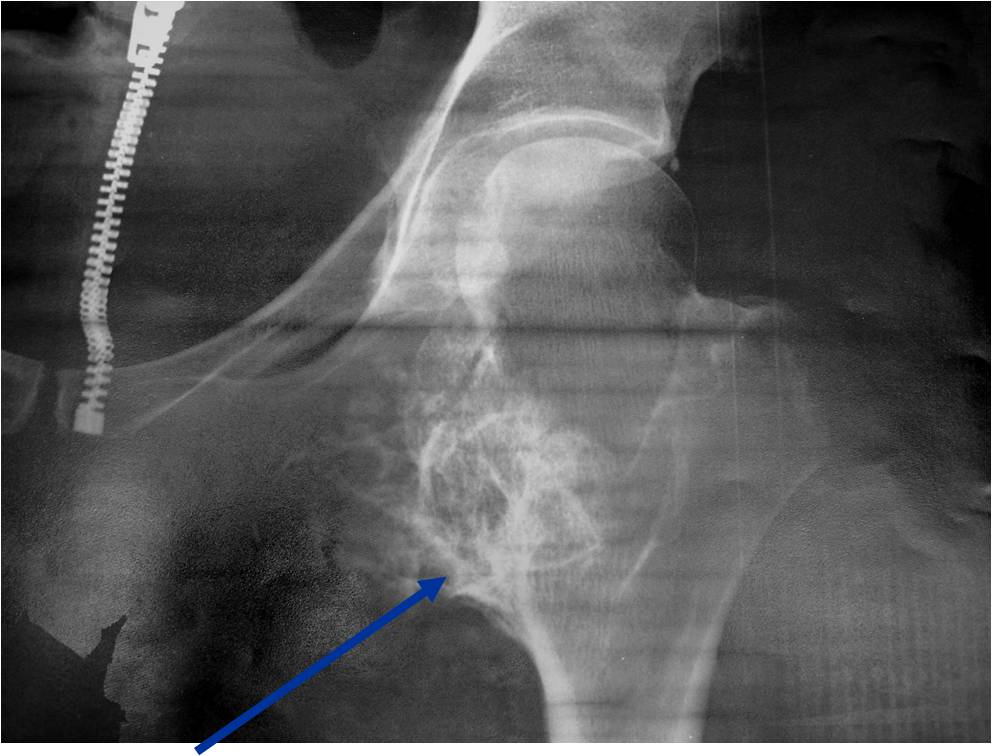

Plain X-ray: Secondary Chondrosarcoma of Proximal Femur

- Projects from bone with narrow (pedunculated) to broad (sessile) stalk

- Corticomedullary continuity: Medullary bone continuous with that of osteochondroma and cortex blends with that of osteochondroma

- Calcification in cartilaginous cap (“Ring and Arc” and stippled calcifications)

- Lobular growth pattern